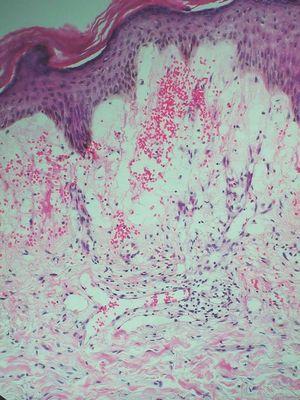

Paciente de 67 años de edad con antecedentes de hipercolesterolemia y anexectomía derecha con ligadura tubárica en 1993. Es intervenida de un carcinoma intraductal de la mama izquierda (T1N0M0) en 1992, por lo cual sufrió una cuadrantectomía superior izquierda junto con una linfadenectomía axilar profiláctica y tratamiento complementario con radioterapia y hormonoterapia (letrozol). En 2004 comienza con lesiones en el miembro superior izquierdo junto con dolor y edema de dicha extremidad. Fue diagnosticada inicialmente de celulitis, recibiendo tratamiento con amoxicilina más ácido clavulánico con mala evolución del cuadro, momento en el cual es valorada por dermatología. La paciente presentaba un importante edema en la extremidad superior izquierda, junto con múltiples pápulas eritematosas de superficie brillante bien definidas (fig. 1). Las lesiones eran asintomáticas y no se habían modificado desde su aparición. Se procedió a la realización de una biopsia cutánea que presentaba múltiples cavidades en dermis papilar y reticular alta que producían una dehiscencia a dicho nivel. Dichas cavidades estaban ocupadas por un material eosinofílico y recubiertas por una capa de células endoteliales que correspondían a vasos linfáticos (fig. 2). Se estableció de esta forma el diagnóstico de linfangiectasias. Las lesiones se resolvieron espontáneamente al cabo de unas semanas, persistiendo el edema de fondo.

Figura 2. Vasos linfáticos en dermis (hematoxilina-eosina,x100).

Histológicamente los vasos linfáticos presentan una pared fina de células aplanadas con núcleos más espaciados a diferencia de los del endotelio vascular. Suelen estar vacíos o presentar en su interior un material eosinofílico homogéneo (linfa) con eritrocitos escasos o ausentes. También son característicos los canales dilatados de forma irregular. No existe capa muscular ni presencia de cuerpos de Weibel-Palade (estructuras en forma de varilla presentes en vénulas o arteriolas). Para algunos autores, las linfangiectasias constituirían una entidad independiente desde el punto de vista histológico por la ausencia de cisternas subcutáneas, las cuales están presentes en el linfangioma circunscrito6,11; para otros, son procesos idénticos que únicamente se diferenciarían entre sí a través de la historia clínica20,22. Inmunohistoquímicamente se diferencian de los hemangiomas por presentar factor VIII negativo y anti-CD34 positivo. El Ulex europaeus I es positivo en los dos.